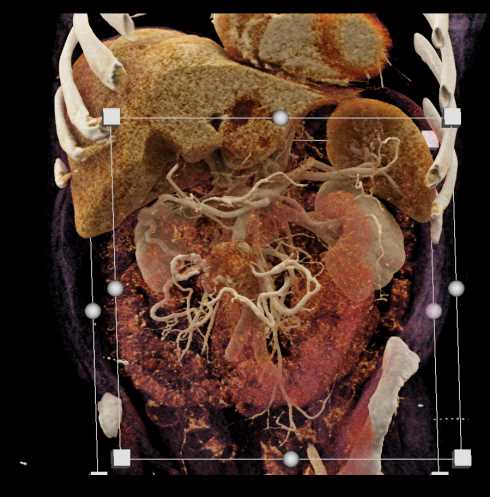

Carcinoid Tumor with Desmoplastic Reaction